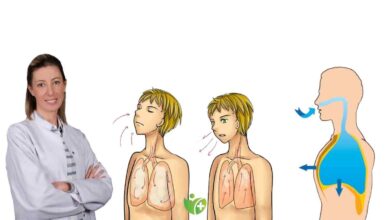

SİGARA İÇEN HERKES LARİNKS KANSERİ OLUR MU?

Sigara içen herkesin larinks kanseri olması söz konusu değildir, daha önce belirtildiği gibi genetik yatkınlığı olan kişiler sigara içtiğinde bu olasılık belirli ölçüde artar. Sigara uzun dönemde bütün solunum yolu mukozasında, akciğer de dahil, olumsuz değişikler oluşturur. Bu olumsuzluklar zaman içinde kansere dönüşebilir; bu süreç HPV, sesin kötü kullanımı, genetik yatkınlık gibi diğer faktörler de eşlik ettiğinde daha hızlanabilir.